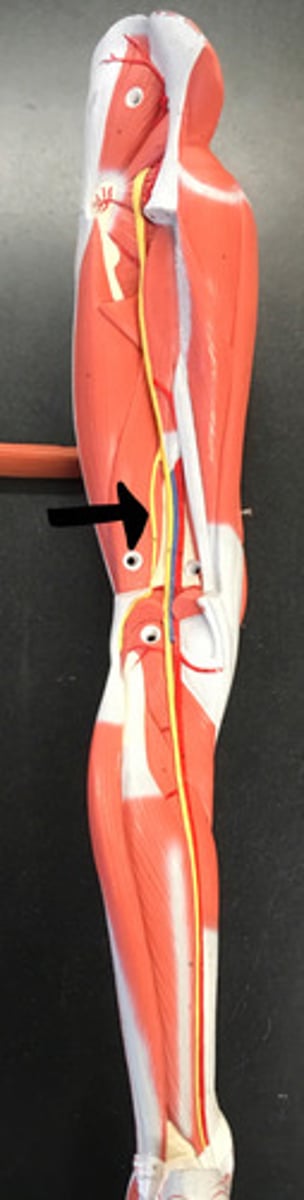

femoral nerve

saphenous nerve

sciatic nerve

common fibular nerve

tibial nerve